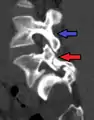

Anterolisthesis L5/S1

Anterolisthesis L5/S1. Blue arrow normal pars interarticularis. Red arrow is a break in pars interarticularis.